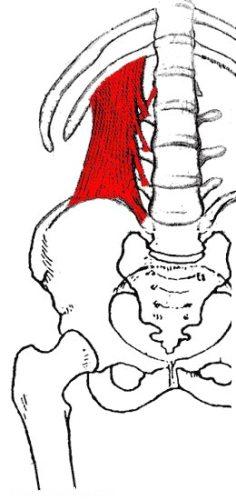

عضله مربع کمری

عضله ای پهن است که در دو طرف ستون فقرات در ناحیه کمر قرار دارد. این عضله از روی بخش خلفی تاج خاصره شروع شده و با چسبندگی روی زوائد عرضی مهره های اول تا چهارم کمر روی لبه تحتانی دنده دوازدهم متصل می گردد.